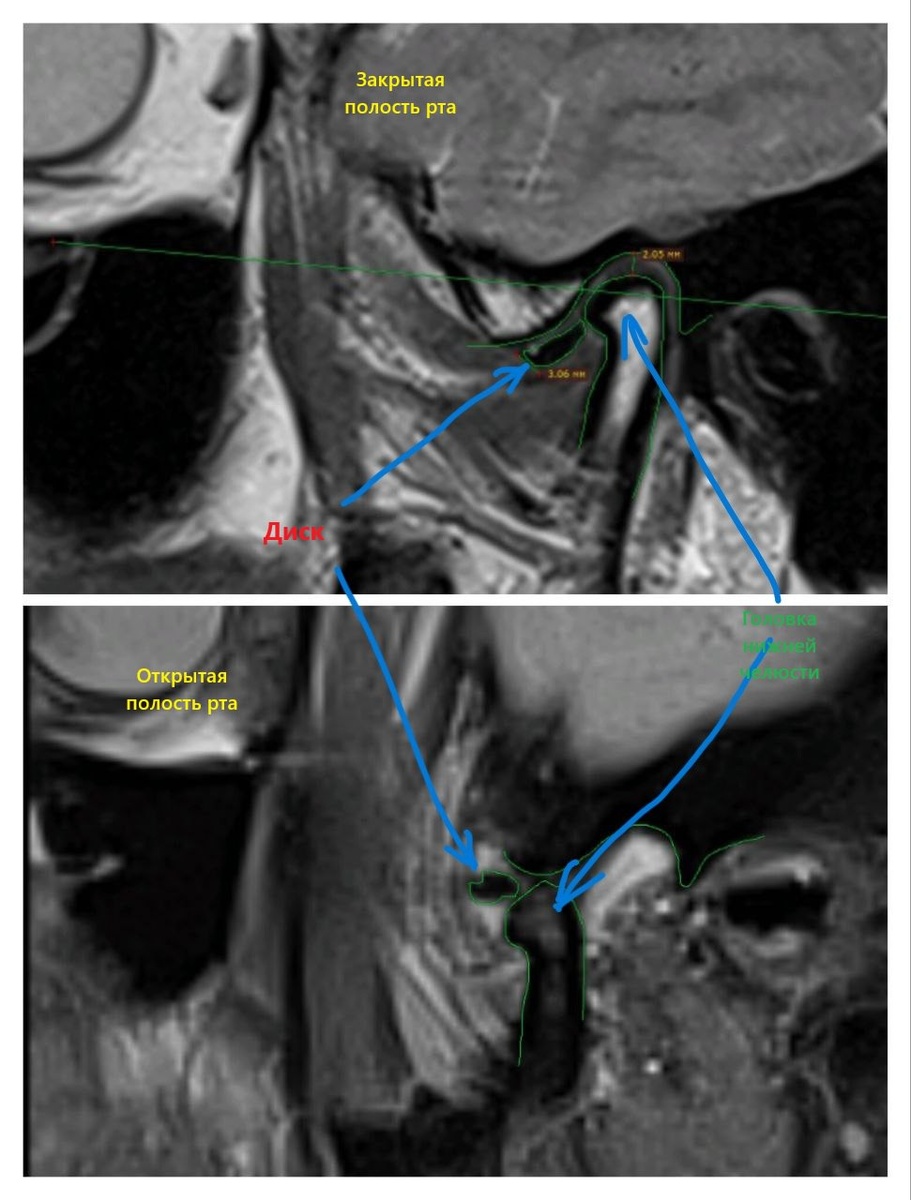

2 коллаж левая сторона: Суставной диск не

смещен в передне-заднем направлении, в корональной плоскости не смещен, МР-сигнал от него

При открывании рта суставной диск занимает нормальное положение, расположен междусуставными поверхностями.